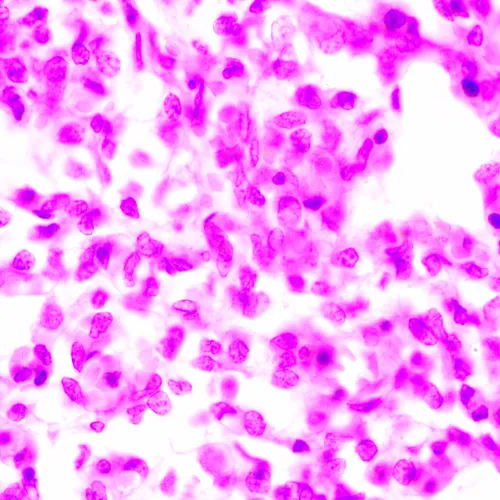

Изследователски клас микроскоп. Конструиран за наблюдение на прозрачни и полупрозрачни биологични проби, като например натривки и напречни сечения в преминаваща светлина по метода на светлото поле. Монтирането на допълнителни принадлежности ще осигури възможност за използване на методите на тъмното поле, фазовия контраст, флуоресценцията и поляризацията.

• Наблюдение на прозрачни и полупрозрачни образци по метода на светлото поле с пропусната светлина